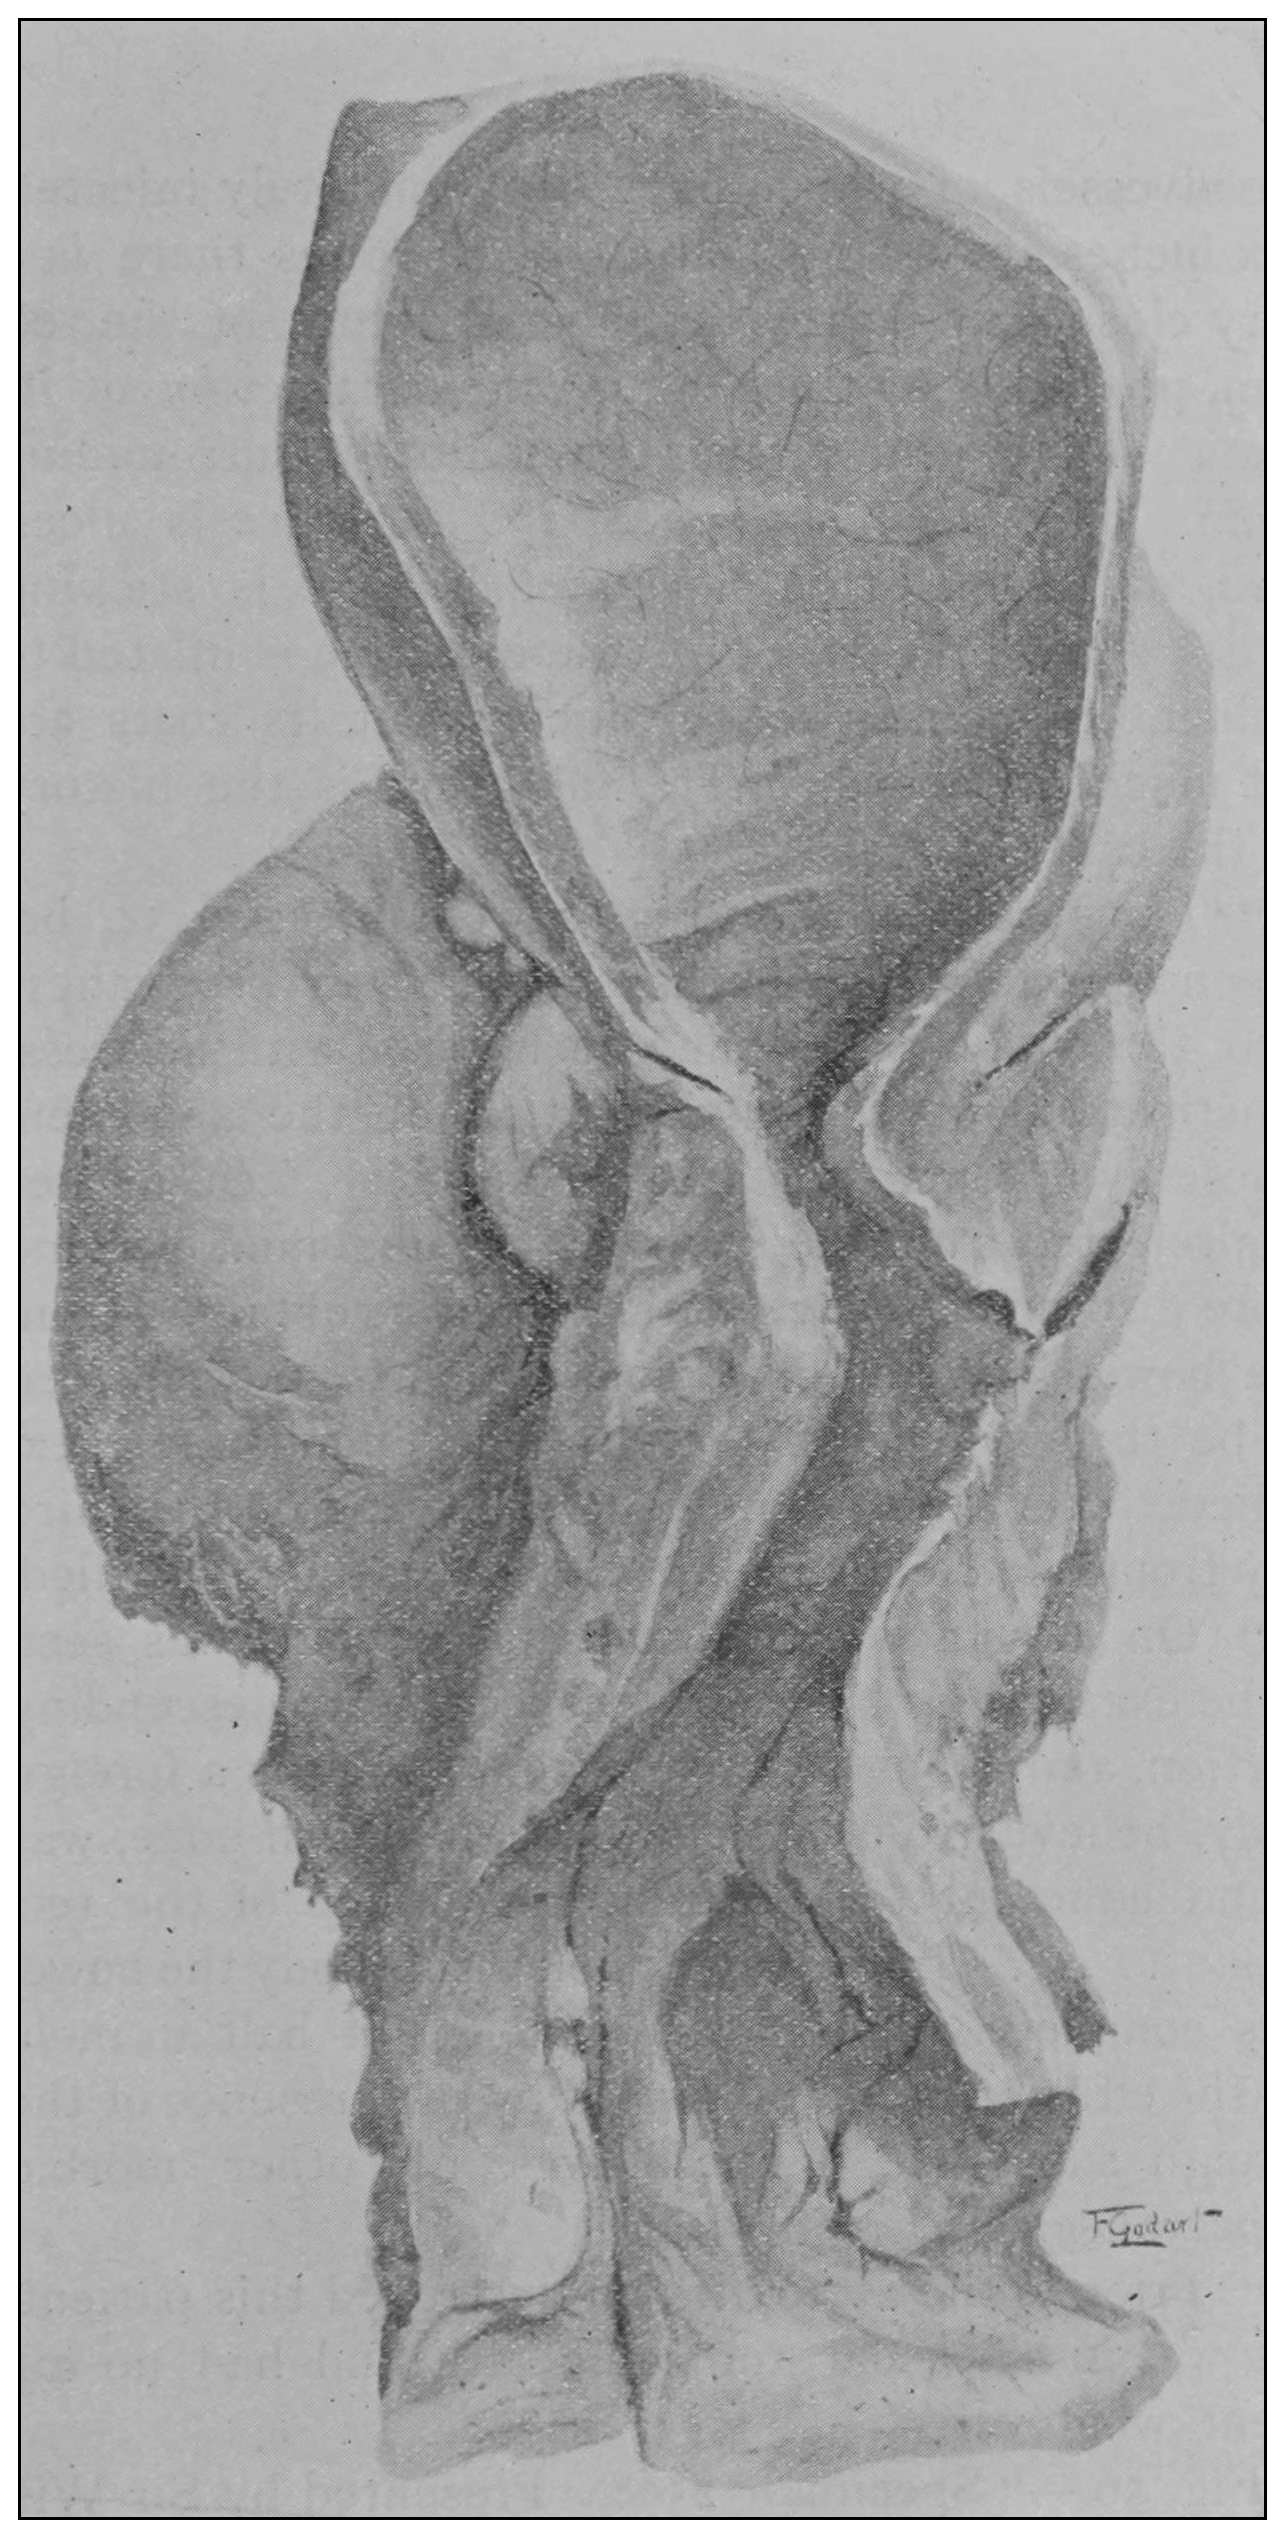

Houston distended and hardened the rectum in situ with spirit. On mesial section of the subject the gut presented valve-like folds with unvarying constancy but in varying number, and in different location in different subjects. He declared their structure to be a duplicature of mucous membrane and bundles of circular muscular fibers only. Others recognizing that in moderate distention the mucous membrane is loosely adherent in the lower rectum, insist that under the conditions employed by Houston the membrane would assume the same appearance as that described by him, and therefore conclude that these features are accidental folds and not valves; and, as Houston did not support his statement by attributing to these valves the histologic element which histologists recognize as the essential feature of a valve, the opinion of[30] his opponents is seemingly reasonable, but is nevertheless a mistake.

Velpeau supported Nelaton’s claim for the superior sphincter by removing the rectum and turning it inside out, so that its mucous membrane was external, and then by inflation demonstrated a marked constriction on the now external surface, which was distinctly claimed to be nothing other than a muscular band. It is not difficult to understand how the true valve within the normally situated gut would appear as a constricting band when the rectum is removed and turned in the manner described.

The photographic reproductions here published are documentary evidence of the existence of the obstructions under discussion. The sketch, Fig. 33, which was drawn from the valve while under the microscopic lens, exhibits the character of these obstructions and proves it that of a typic anatomic valve, and the absence of permanent bands of any other character in this organ is evidence that the semilunar valves and the so-called plica transversalis recti, Falten des Rectums, sphincter ani tertius, superior sphincter, and detrusor fecium muscles are one and the same thing and this thing is essentially a valve. It is most prominent when the gut is most distended.